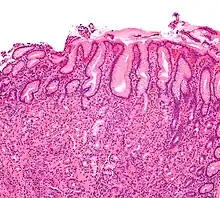

| Micrograph showing gastritis. H&E stain. | |